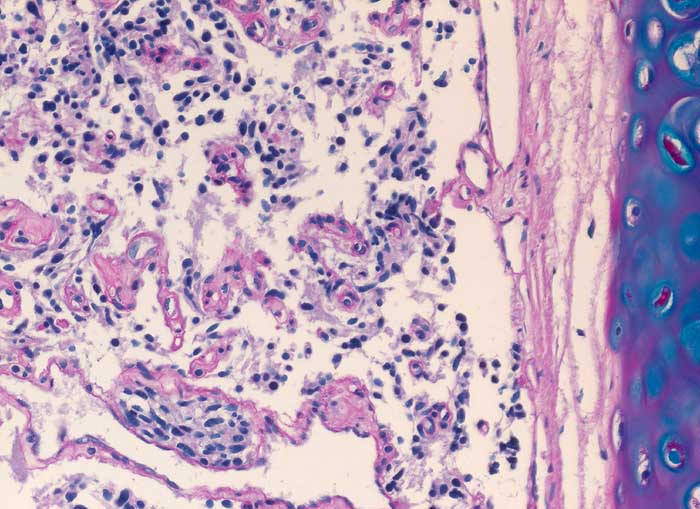

Karzinoid

Spindelzellige Tumorzellnester bilden kleine von schmalen Bindegewebssepten mit Kapillaren umgebene Zellnester. Der Tumor infiltriert die Submukosa.

Da es sich nur um eine sehr kleine Biopsie handelt, kann ein atypisches Karzinoid (Nekrosen, Mitosen) nicht ausgeschlossen werden.

Histologie

200